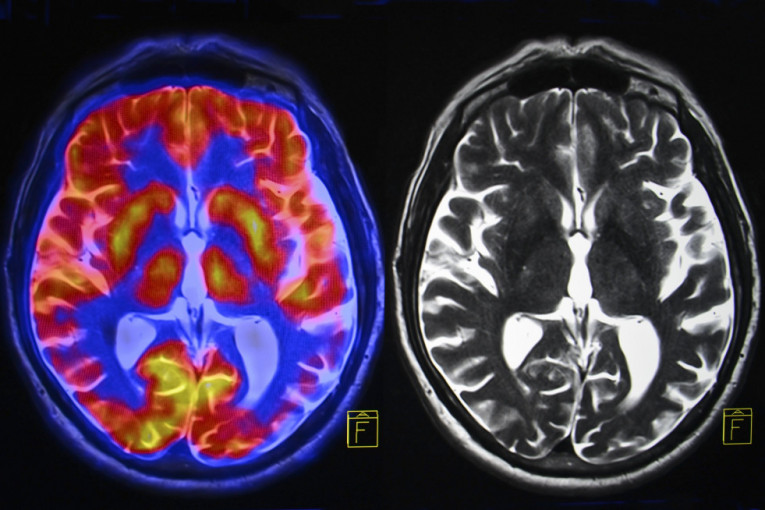

CT i MRI snimci otkrili su prisustvo cisti u mozgu, a dijagnoza je bila neurocisticerkoza, parazitska infekcija koja može nastati konzumiranjem zaraženog mesa. Lekari veruju da je parazit ušao u telo pacijenta nakon konzumiranja nedovoljno pečene slanine i putovao iz creva do mozga krvotokom, piše "Miror".

Na skeneru mozga su uočene promene